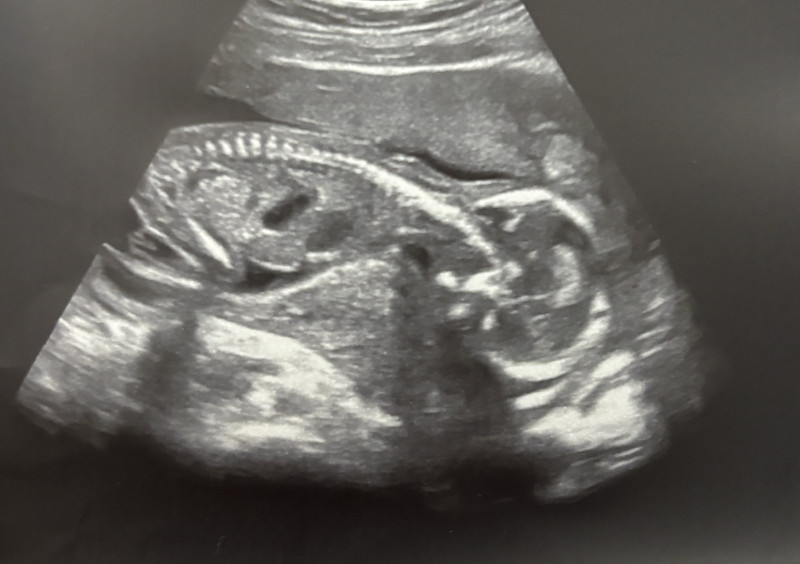

- Nėštumas